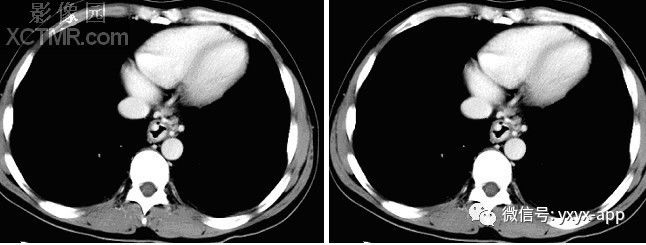

CT增强动脉期

CT增强门脉期

【影像表现】X线吞钡:食管下段迂曲,管壁呈锯齿状改变,粘膜皱襞增宽、增粗,扭曲呈蚯蚓状,并可见串珠状充盈缺损,食管稍扩张,管壁轮廓凹凸不平,钡剂排空延迟。管壁柔软,舒缩功能良好。 CT平扫及增强扫描可见食管内多发类圆形稍低密度病灶,动脉期未见明显强化,门脉期强化明显,与同层面主动脉强化程度相仿,显示病灶为血管性病变。肝脏大小比例失调,肝表面结节样不平,肝内密度尚均匀,未见明显局灶性密度异常及异常强化。